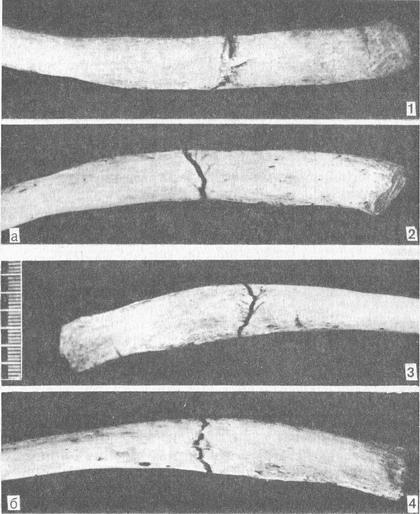

Множинні переломи ребер можуть виникати як при неодноразовому зовнішньому впливі (частіше ударах), так і при одноразовому (зазвичай при здавленні). В останньому випадку переломи ребер розташовуються як би по одній або декількох анатомічних лініях. Щодо особливостей переломів ребер можливо диференціювати умови, при яких вони виникли (табл. 7, рис. 30).

| Контур краю перелому | У вигляді різко ламаної лінії, орієнтованої косопоперечно до поздовжньої осі ребра. Зіставлення відламків неповне, з дефектом речовини компакти аж до утворення осколків | Дрібнозубчатий у вигляді прямої поперечної або косопоперечной лінії; в задніх відділах (на внутрішній стороні) частіше дугоподібна. Зіставлення відламків повне |

| Тріщини | Рідко поздовжні | Відходять від перелому під гострим кутом у напрямку до краю ребра |

| Осколки | Ромбоподібний (профіль - трикутник) | Відсутні |

| Поверхня зламу | Крупнозубчатая | Дрібнозерниста або дрібнозубчаста |

| Площина зламу | Коса але відношенню до поверхні ребра | Перпендикулярна по відношенню до поверхні ребра |